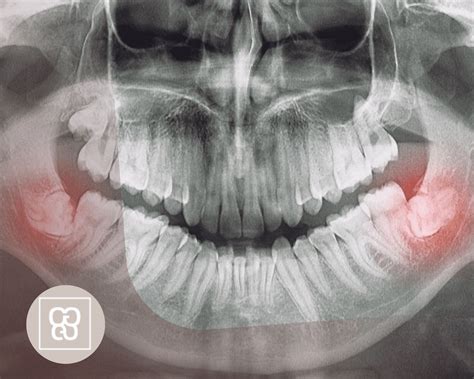

Tecnología avanzada para una evaluación precisa

En algunos centros de diagnóstico, la evaluación de la necesidad de extracción se realiza con equipos de diagnóstico de última generación, como el escáner NewTom GiANO HR. Este equipo permite realizar imágenes 3D de alta precisión de la estructura ósea de la mandíbula y los dientes. Así se facilita una visión clara de la posición exacta de las muelas del juicio y su relación con los nervios y otras estructuras vitales.

La utilización de este tipo de tecnología avanzada contribuye significativamente a mejorar los resultados quirúrgicos. Al proporcionar imágenes precisas, el escáner permite a los cirujanos realizar incisiones más precisas, lo que lleva a una reducción en los tiempos de recuperación postoperatorios y una mejor experiencia general para el paciente.